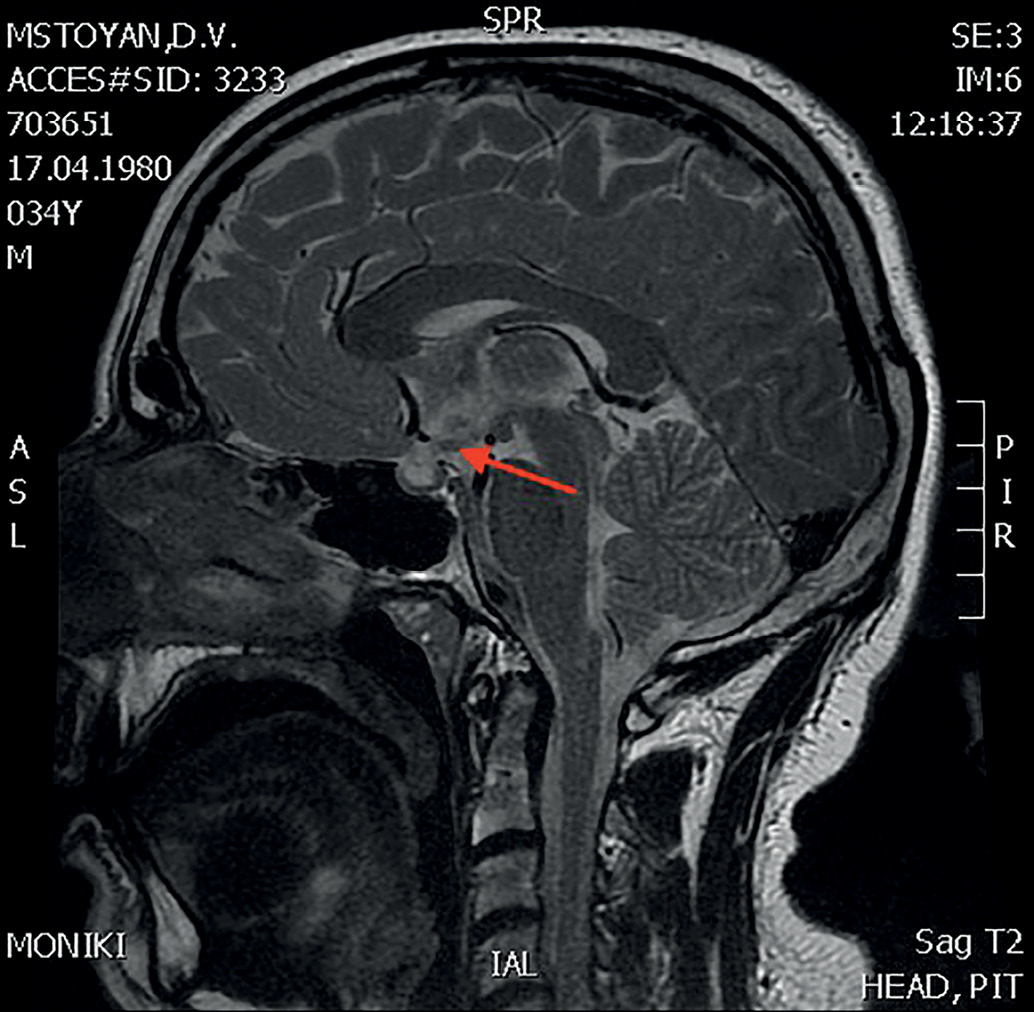

В 34 года (в 2014 г.) впервые появились жалобы на выраженную жажду (до 7 л в сутки), учащенное обильное мочеиспускание, сухость во рту, головную боль, сохранялась общая слабость. Выполнен анализ суточной мочи по Зимницкому, по результатам которого плотность мочи составила 1001–1003, общее количество мочи за сутки – 6 л. Выполнена МРТ головного мозга с контрастированием от 03.10.2014: образование в проекции гипоталамуса, сосцевидных тел и прилежащих отделов воронки увеличилось в размерах, «пустое» турецкое седло, характерной яркости МР-сигнала в области нейрогипофиза не отмечено (рис. 1). Уровни гликемии, калия и кальция в пределах референсных значений. Диагностирован несахарный диабет центрального генеза. Дополнительно к проводимой заместительной терапии назначен десмопрессин 0,2 мг 2 раза в сутки. На фоне скорректированного лечения жажда, учащенное мочеиспускание, сухость во рту не беспокоили, диурез менее 3 л, уменьшилась общая слабость.

Рисунок 1. МРТ головного мозга с к/у от 03.10.2014г.(3,0 Тл)

Саркоидная гранулема в проекции гипоталамуса, сосцевидных тел и прилежащих отделов воронки (указано стрелкой).

Figure 1. MRI of the brain with c/c dated 03.10.2014 (3.0 T)

Sarcoid granuloma in the projection of the hypothalamus, mastoid bodies and adjacent parts of the infundibulum (indicated by an arrow).